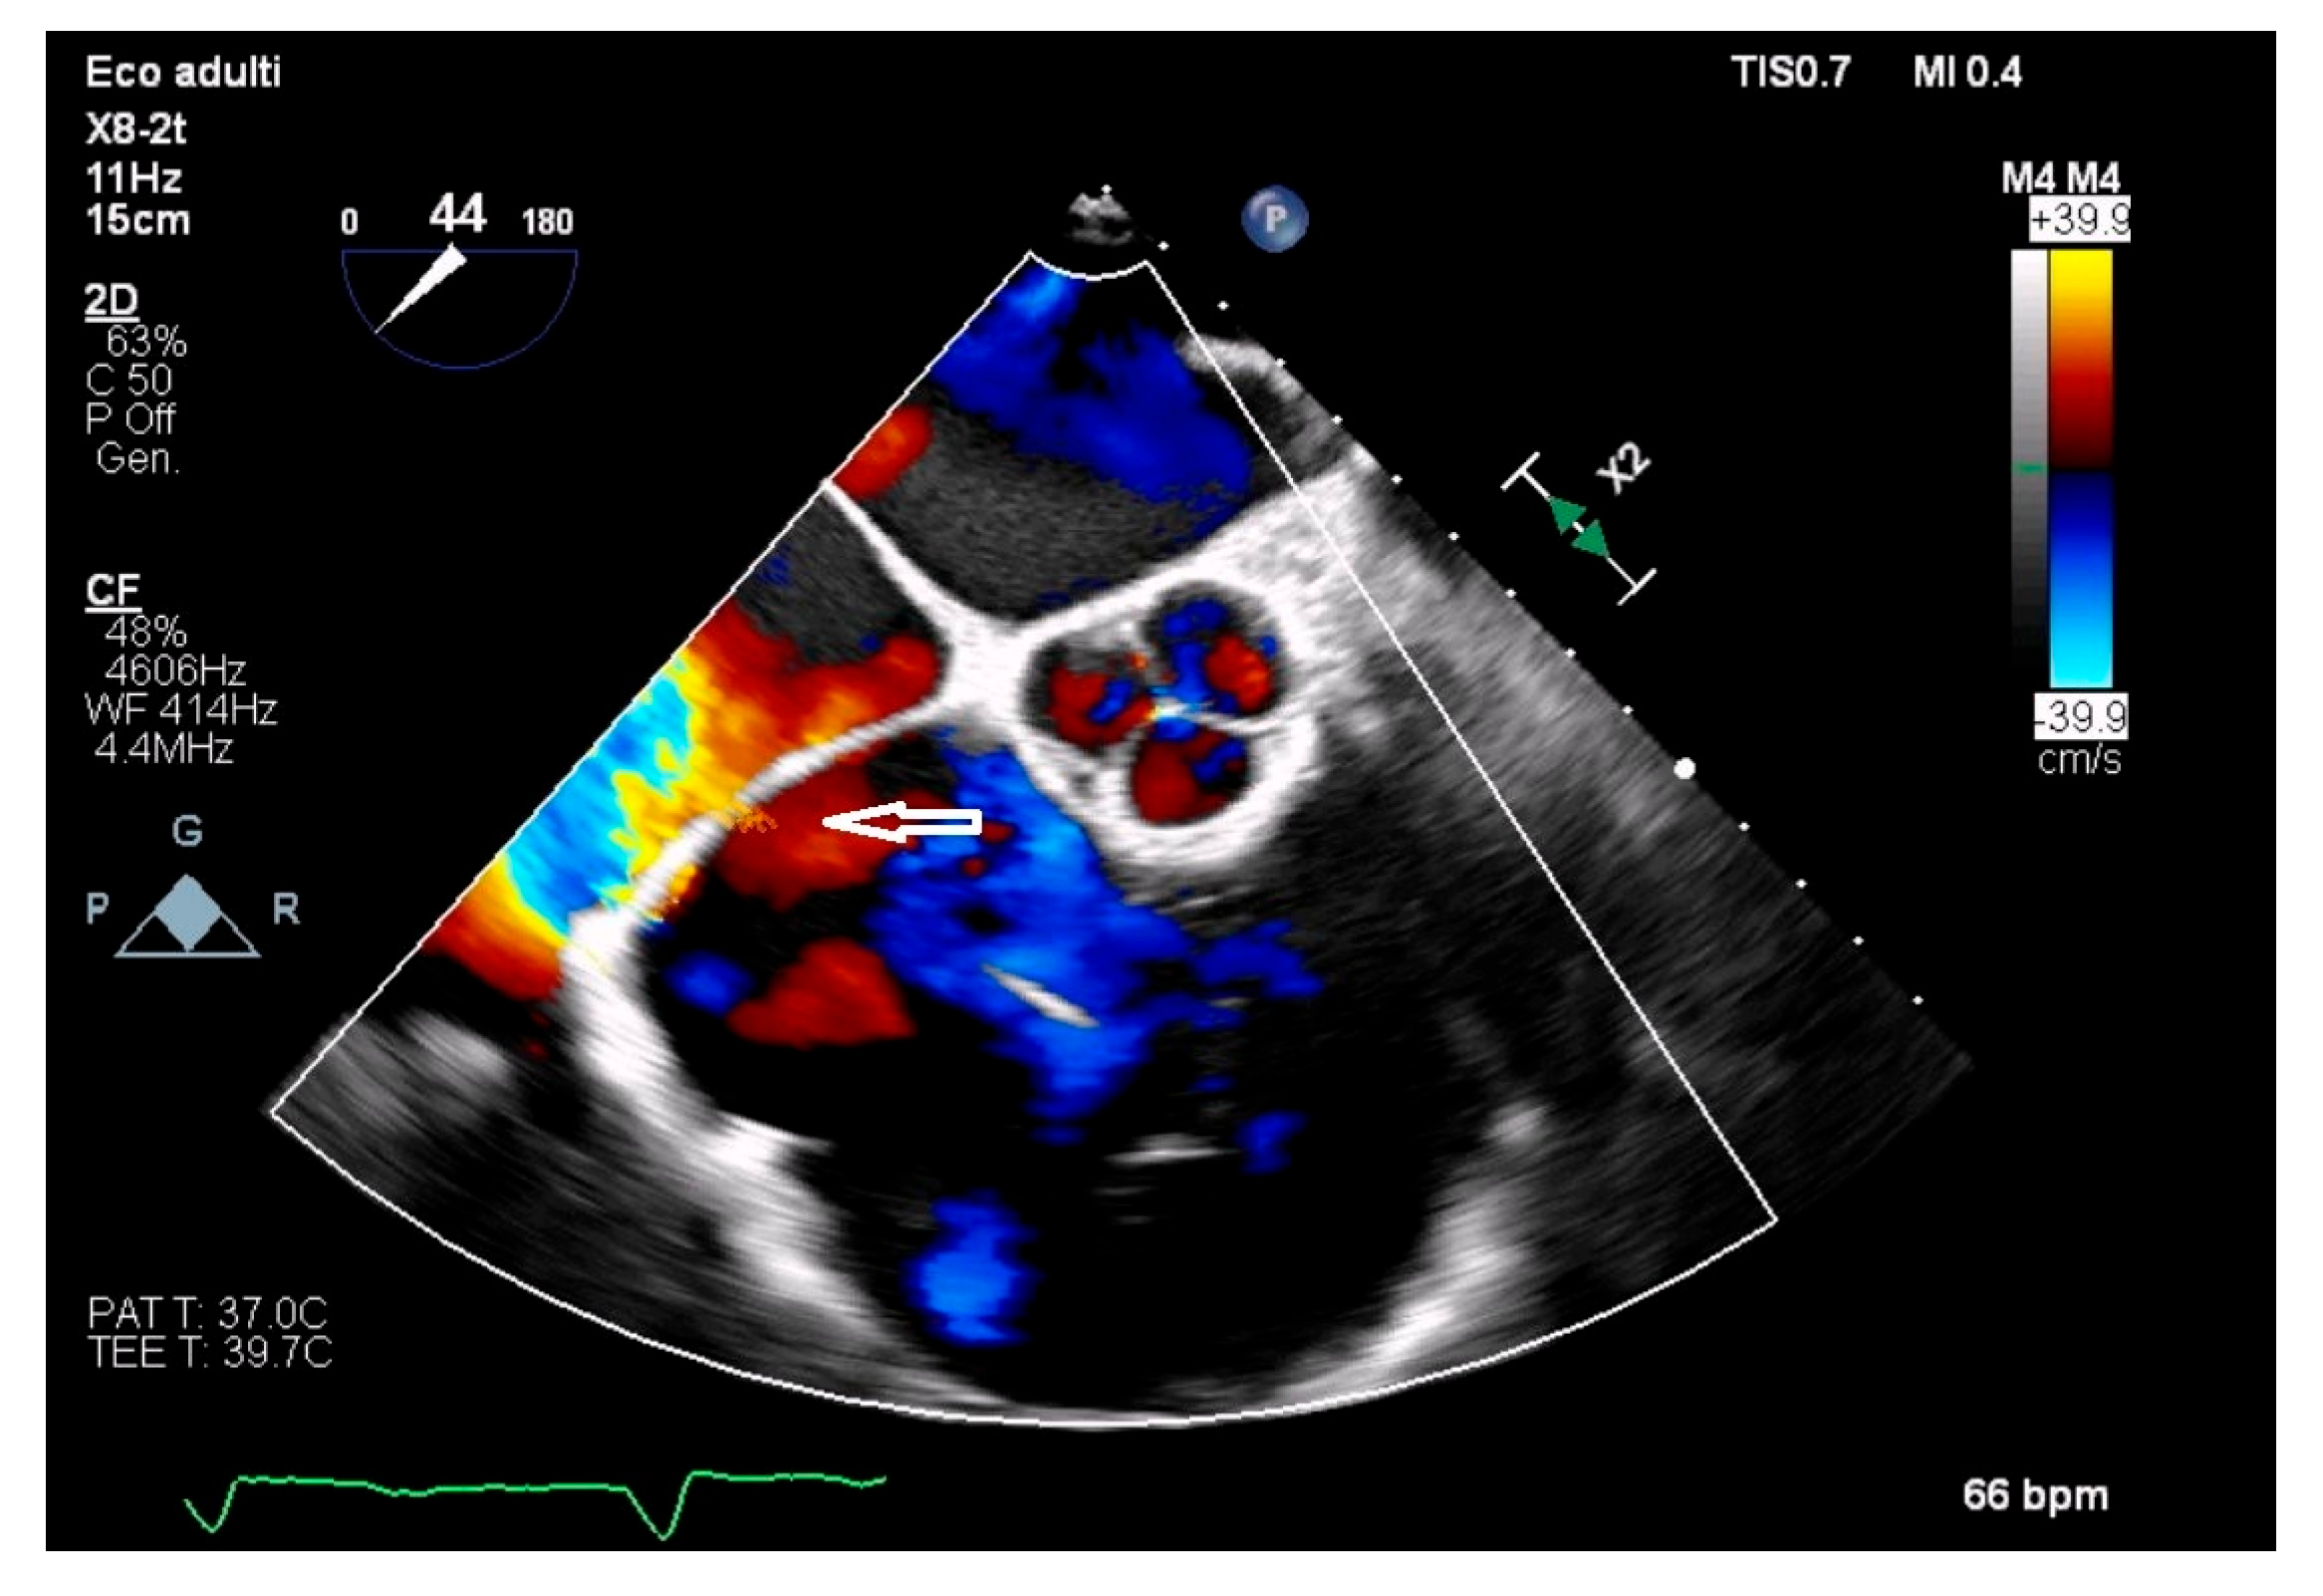

- Franco, E.; Rovera, C.; Moretti, C.; Bassareo, P.P. Arrhythmogenic Right Ventricular Cardiomyopathy and Cor Triatriatum Dexter: An Unreported Association. Clin. Case Rep. 2025, 13, e71159. [Google Scholar] [CrossRef]